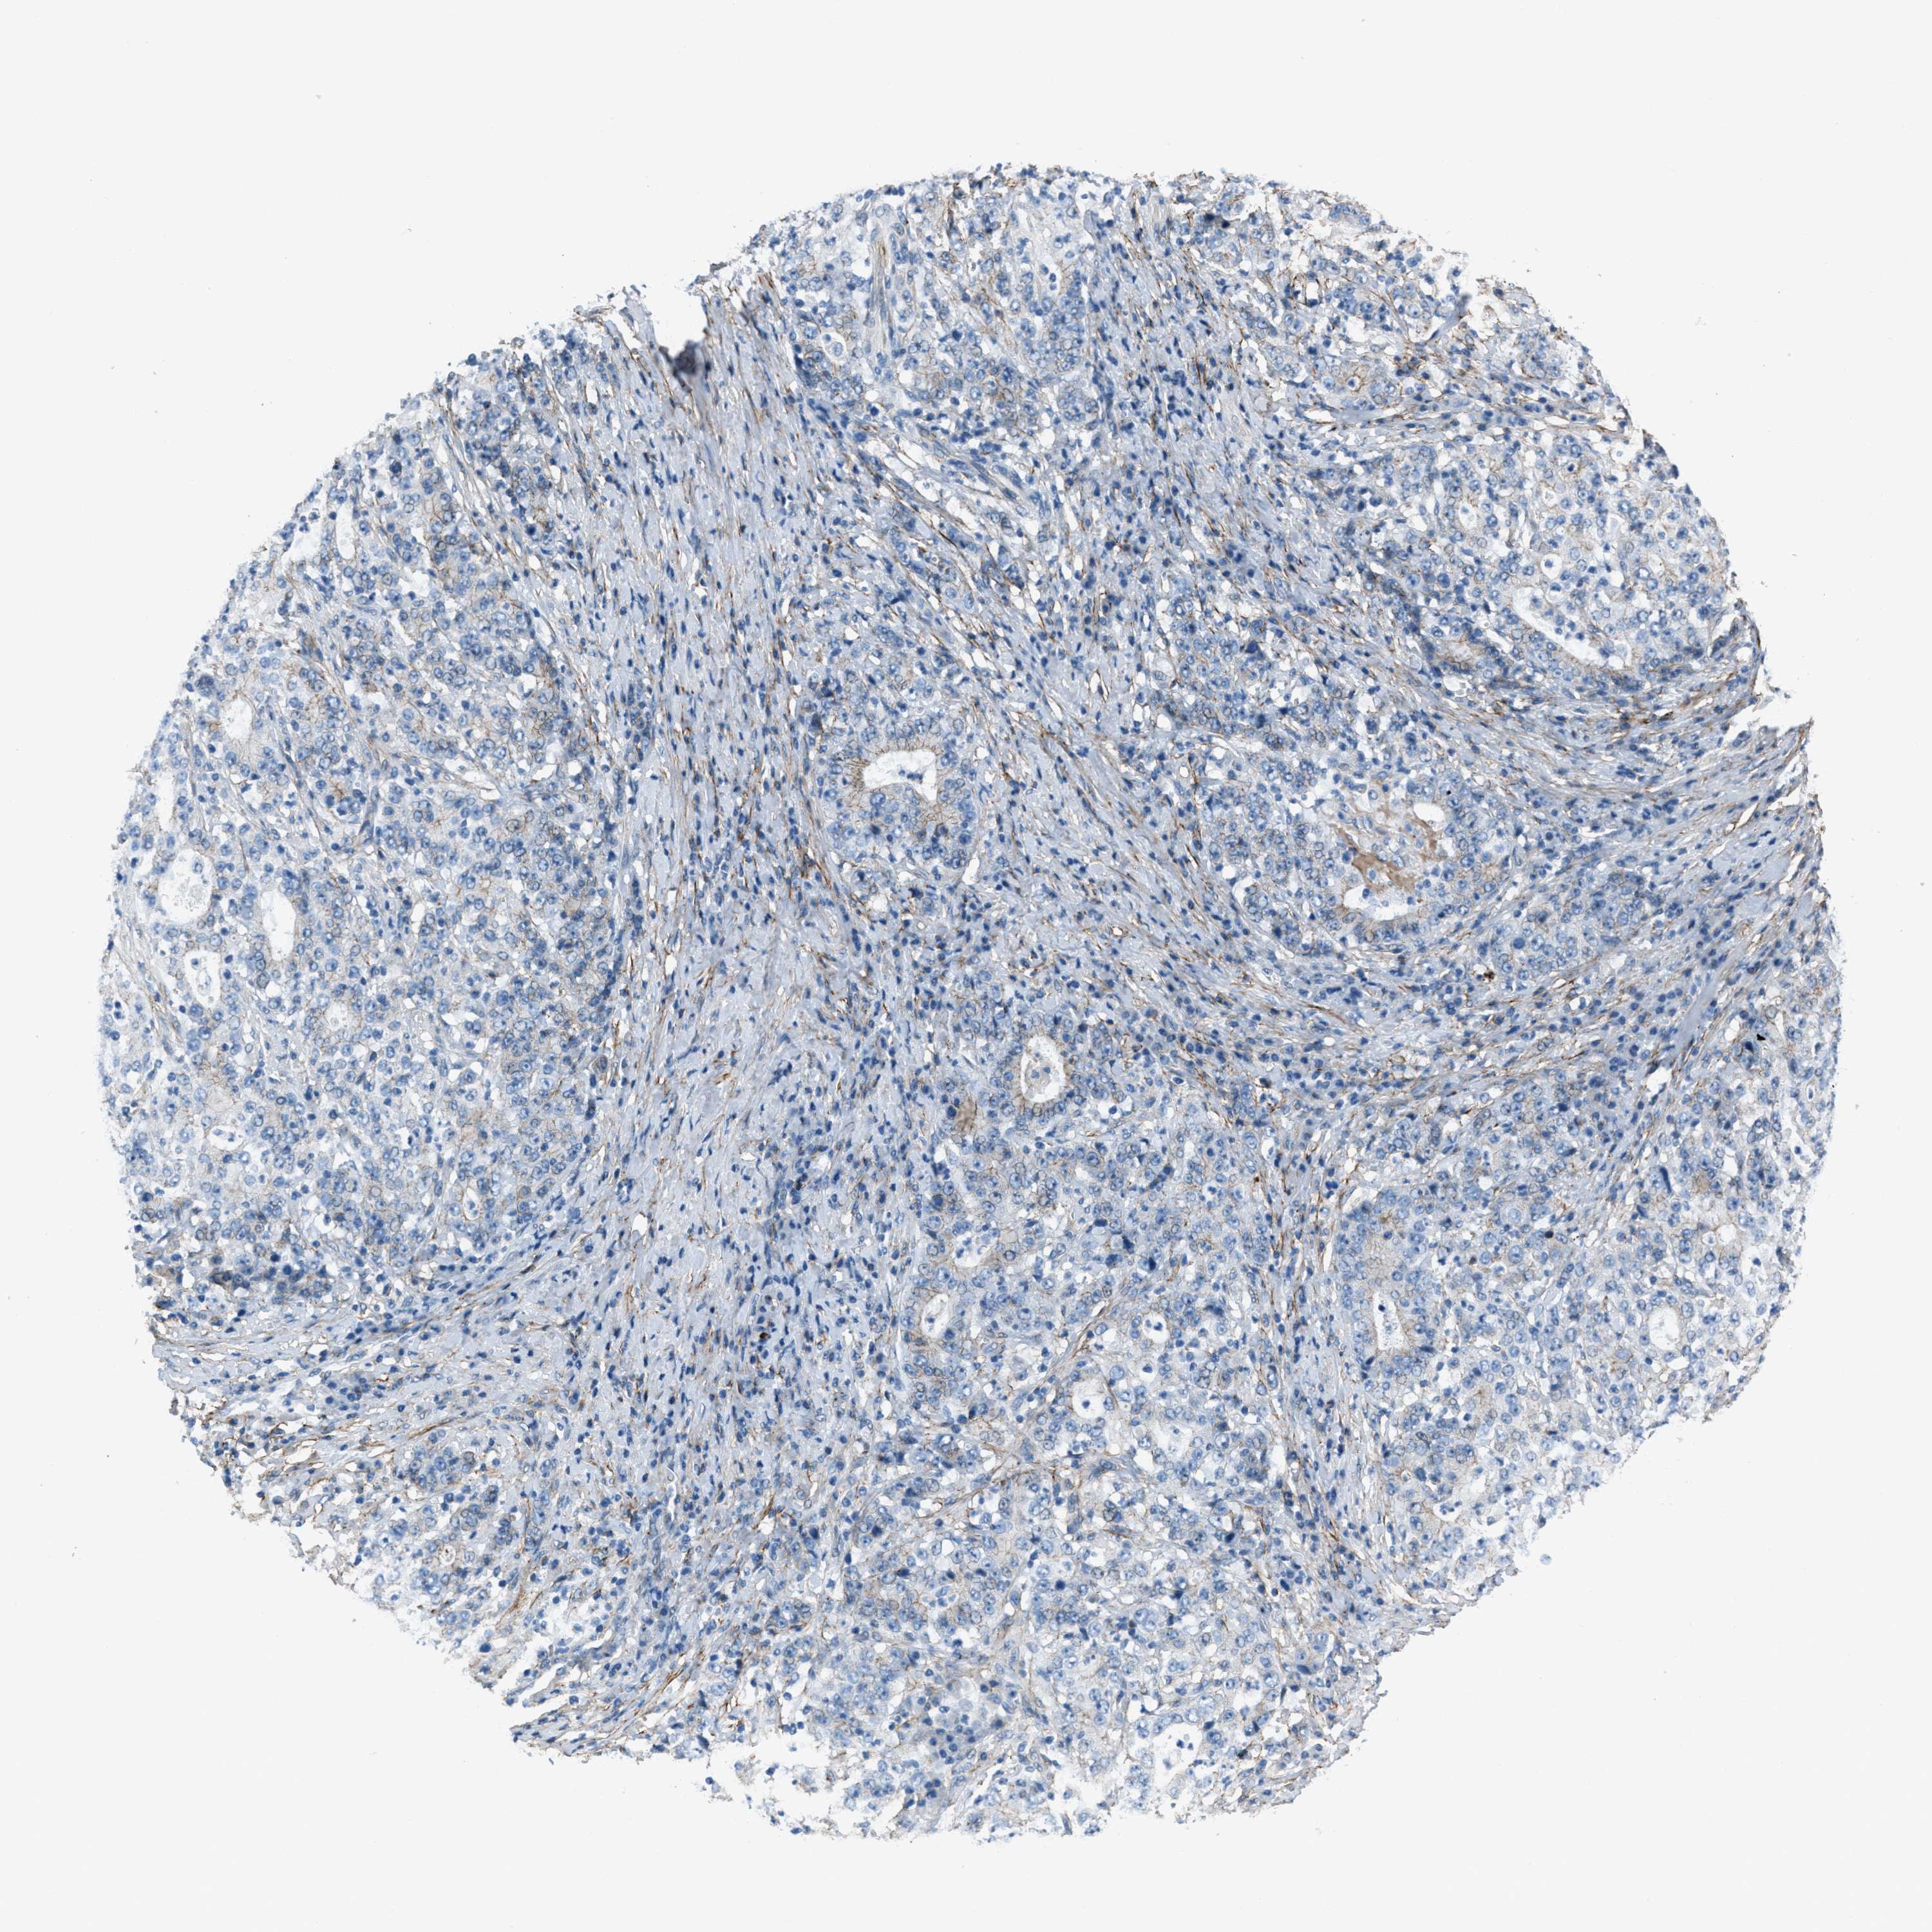

STOMACH CANCER - Protein expressioni

A mouse-over function shows sample information and annotation data. Click on an image to view it in a full screen mode. Samples can be filtered based on level of antibody staining by selecting one or several of the following categories: high, medium, low and not detected. The assay and annotation is described here.

Note that samples used for immunohistochemistry by the Human Protein Atlas do not correspond to samples in the TCGA dataset.

Antibody stainingi

Antibody staining in the annotated cell types in the current human tissue is reported as not detected, low, medium, or high, based on conventional immunohistochemistry profiling in selected tissues. This score is based on the combination of the staining intensity and fraction of stained cells.

Each image is clickable and will lead to virtual microscopy that enables deeper exploration of all samples and also displays staining intensity scores, fraction scores and subcellular localization as well as patient and tissue information for each sample.

Staining

High

Medium

Low

Not detected

Intensity

Strong

Moderate

Weak

Negative

Quantity

>75%

75%-25%

<25%

None

Location

Nuclear

Cytoplasmic/membranous

Cytoplasmic/membranous,nuclear

Adenocarcinoma, NOS

Adenocarcinoma, High grade